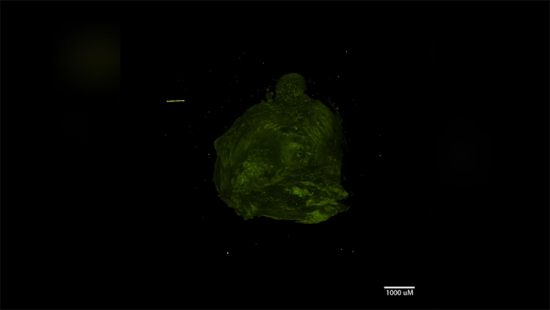

Опухоли молочной железы, с которых исследователи планируют начать, сперва будут разрезаться на очень тонкие части, которые затем можно будет анализировать — вплоть до генетического состава каждой отдельной клетки. Каждая часть может быть представлена в виде трёхмерной модели, которую исследователи могут с лёгкостью осматривать в режиме виртуальной реальности.

Трёхмерные модели опухолей и других раковых новообразований уже существуют, но кембриджские учёные планируют реализовать всё на гораздо более детализированном и интерактивном уровне.